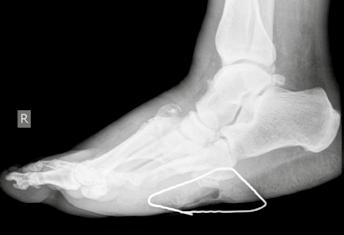

Die Charcot-Arthropathie bzw. neuropathische Osteoarthropathie (NOAP) des Fußes und Sprunggelenkes ist eine schwerwiegende Form des Diabetischen Fußsyndroms. Es ist ein deformierender und zerstörerischer Prozess auf dem Boden einer Polyneuropathie, der zu gravierenden Instabilitäten, rezidivierenden Ulzera und bakteriellen Superinfektionen führen kann (Abb. 1). Schlussendlich kann dieses Erkrankungsbild bis zur Amputation führen. Ziel der Behandlung des Charcot-Fußes ist es daher, eine Amputation zu verhindern. Dies gilt vor allem für die Majoramputation, da dieser Eingriff insbesondere beim diabetischen Patienten statistisch signifikant mit erhöhter Morbidität und Mortalität einhergeht 123.

Zur topographischen, rein radiologischen Einteilung nach Befallsmuster wird meist die Klassifikation nach Sanders u. Frykberg verwendet. In Anlehnung an die Unterteilung von Sanders wird die diabetisch-neuropathische Osteoarthropathie in fünf Haupttypen klassifiziert, die den Hauptprädilektionsstellen der Erkrankung am Fuße entsprechen. Dabei wird die Häufigkeit für den Befall von Sanders & Frykberg wie folgt angegeben: Typ I = 15 % ‚Typ II = 40 % , Typ III = 30 % , Typ IV = 10 % und Typ V = 5 %. Koller ermittelte ähnliche Ergebnisse in seiner Studie 20. Die häufigsten Veränderungen am Fuß der diabetisch-neuropathischen Osteoarthropathie entfallen somit auf die Typen I, II und III (ca. 80 %). Nicht selten zeigt sich ein kombiniertes Befallsmuster (Abb. 2) 21.

- Typ I: Beim Typ I findet man Knochennekrosen im Bereich der Metatarsophalangealgelenke. Diese Nekrosen können zur sogenannten „candy stick deformity“ („Zuckerstängel-Deformität“) des Knochens führen, mit der Gefahr der knöchernen Durchspießung der Fußsohlenhaut.

- Typ II: Typ II betrifft die Tarsometatarsalgelenke, also den Bereich des Lisfranc-Gelenks, und hat als wesentliche Konsequenz – wie beim Typ III – den Verlust der Rückfußstatik zur Folge. Es kommt häufig zur Ausbildung eines Knick-Plattfußes mit deutlicher Vorfußabduktion.

- Typ III: Beim Typ III der DNOAP ist die Nekrose hauptsächlich auf den Bereich des Chopart-Gelenks, den Bereich zwischen Talus und Os naviculare, begrenzt. Hier entwickelt sich der klassische Tintenlöscherfuß mit völligem Einbrechen des Längsgewölbes und Drucküberlastung in der Mitte der Fußsohle.

- Typ IV: Bei diesem Typ, der zu den selteneren Verlaufsformen zählt, zeigt sich die Veränderung im Bereich des oberen Sprunggelenks (OSG). Es kommt dabei häufig zu massiven Instabilitäten.

- Typ V: Diese seltene Verlaufsform der DNOAP betrifft den Calcaneus und das dazugehörige talocalcaneare Gelenk. Es führt zum Zusammenbrechen dieses Gelenkabschnittes mit der zwangsläufigen Verplumpung des gesamten Rückfußes oder zu Schnabelfrakturen des Calcaneus, bedingt durch den Zug der Achillessehne.